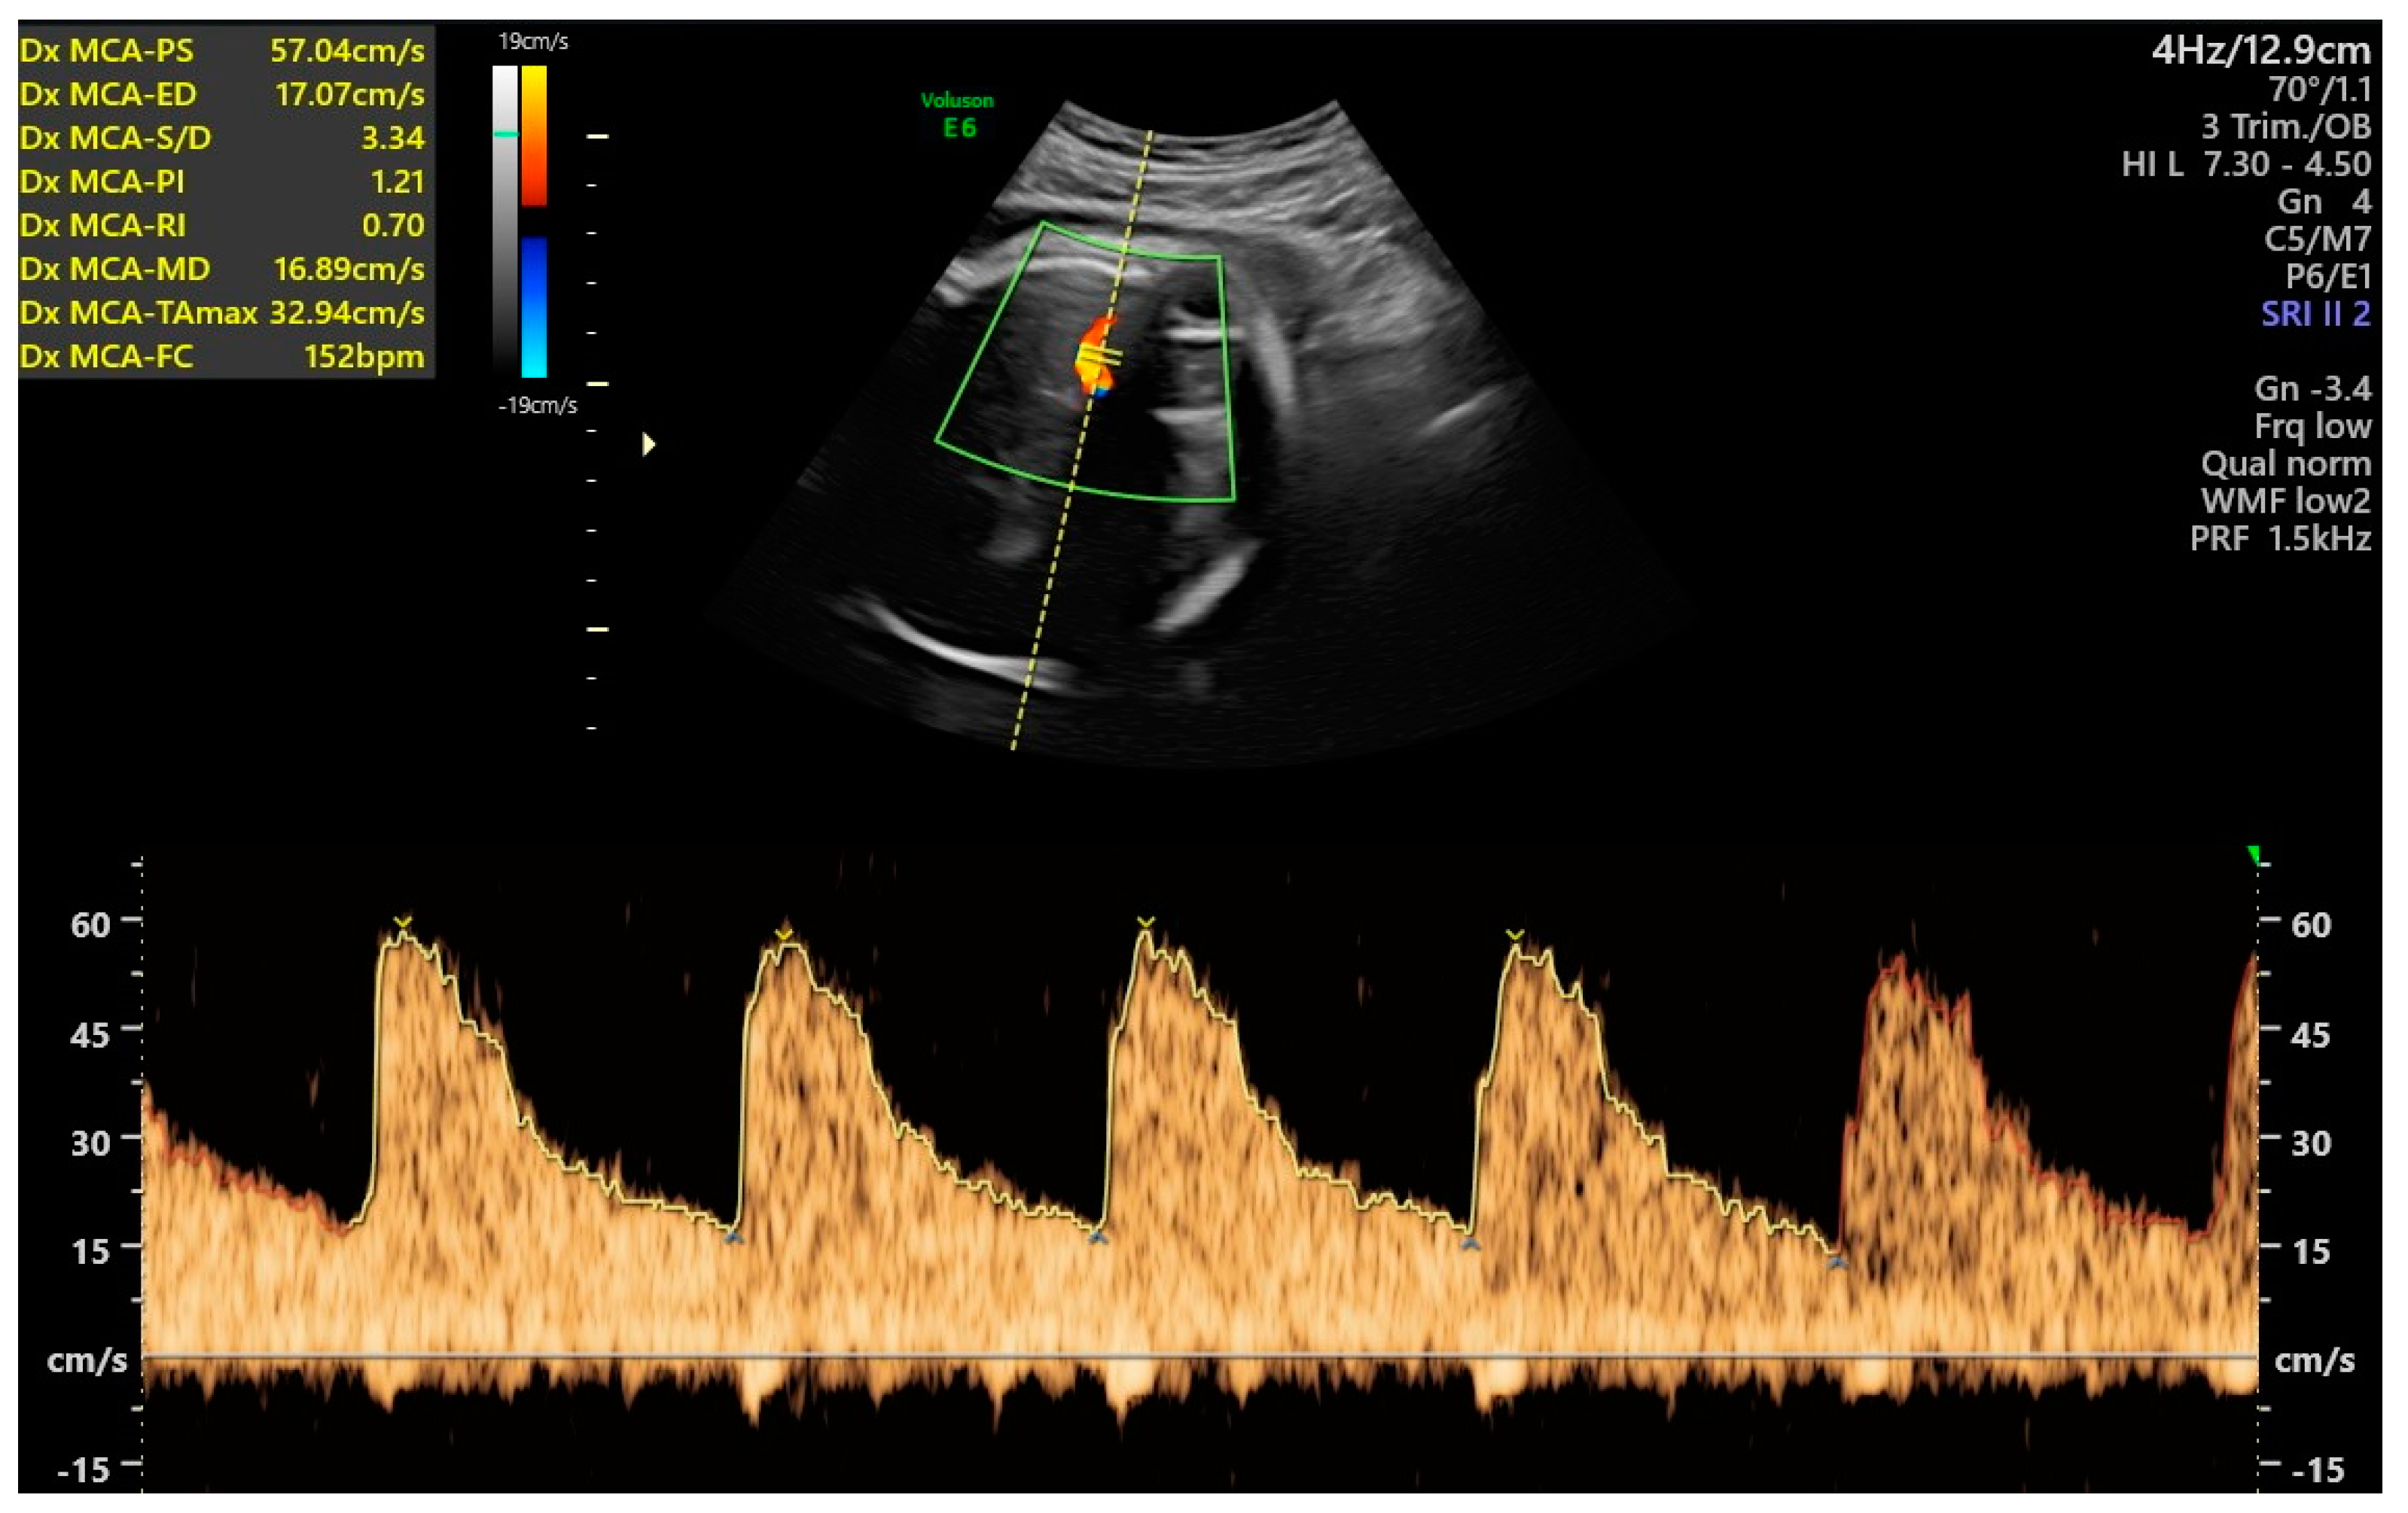

- Ferraguti, G.; Merlino, L.; Battagliese, G.; Piccioni, M.G.; Barbaro, G.; Carito, V.; Messina, M.P.; Scalese, B.; Coriale, G.; Fiore, M.; et al. Fetus morphology changes by second-trimester ultrasound in pregnant women drinking alcohol. Addict. Biol. 2020, 25, e12724. [Google Scholar] [CrossRef]